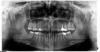

luchik Опубликовано 24 апреля, 2013 Поделиться Опубликовано 24 апреля, 2013 Здравствуйте!На 5-ке ( могу ошибаться с нумерацией) стоит коронка. Последнее время стало иногда несильно ныть между 5 и 6 зубами. Сделали снимок. Сказали воспаление, но из-за чего сказать толком не могут. Предполают, что трещина корня, но на снимке ее не видят. Предлагают удалить и протезировать. Неужели больше ничего нельзя сделать? Зуб жалко! А если воспаление не из-за трещины, то возможен какой-то другой выход или все равно удалять? Ссылка на комментарий

Magdalena Опубликовано 24 апреля, 2013 Поделиться Опубликовано 24 апреля, 2013 Действительно, локализация воспалительного очага похожа на трещину. Вам нужен опытный врач, который может извлечь штифтовкладку и под микроскопом оценить состояние тканей на предмет трещины. Так же можно попробовать посмотреть трещину на компьютерной томограмме. Если тещина - 100% удаление, чем раньше - тем больше сохраниться кости для последующей имплантации. Ссылка на комментарий

Magdalena Опубликовано 12 мая, 2013 Поделиться Опубликовано 12 мая, 2013 У коронки действительно есть нависающий край в межзубном промежутке, если под него забивается пища и налет, воспаление может быть, но такая локализация и объем - вряд ли. Давно делали коронку? Ссылка на комментарий